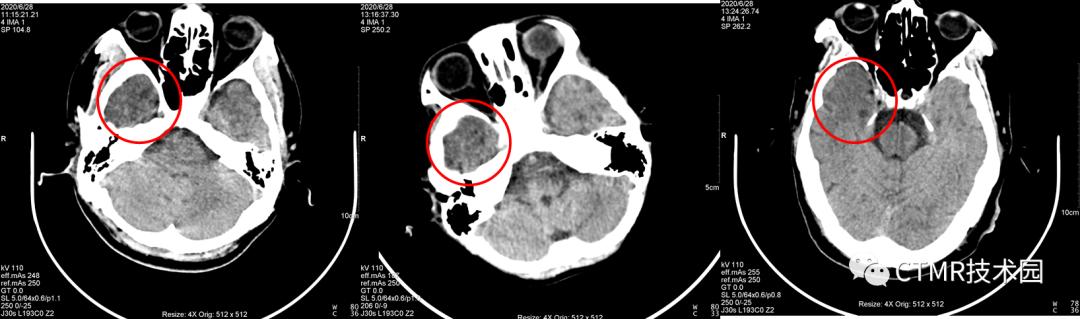

我们有一台西门子 SOMATOM Perspective 64 CT,从装机到现在四五年了,颅脑螺旋扫描条件扫描颅脑,在右侧颞区始终有“暗区”伪影,十分诡异。

而且选用 0.35螺距 eMode 是绿色;如果用 1.1 螺距,那么 eMode 是黄色;如果应用 Adjust,eMode 也变成绿色,且此时当前病人配给的螺距为 0.9,那么它好吗?其实扫描出来的图像大多还是有伪影(从本文开头贴的图片中,有好几个都是 Adjust 后匹配螺距扫描出来的伪影图像)。

探测器宽度约为 4cm,那么在扫描颞部这一区域时,由于螺距 = 1.1>1,或 = 0.9≈1,X 线光子经过对侧的颞区骨头衰减后到达右侧变硬,而且所使用的 kV 是 110kV,不是很高的千伏。又由于颅底这个区域骨质复杂多样,“四面环骨”,那么在右侧的这部分脑组织吸收的 X 线就减少,从而就表现为“暗区”。